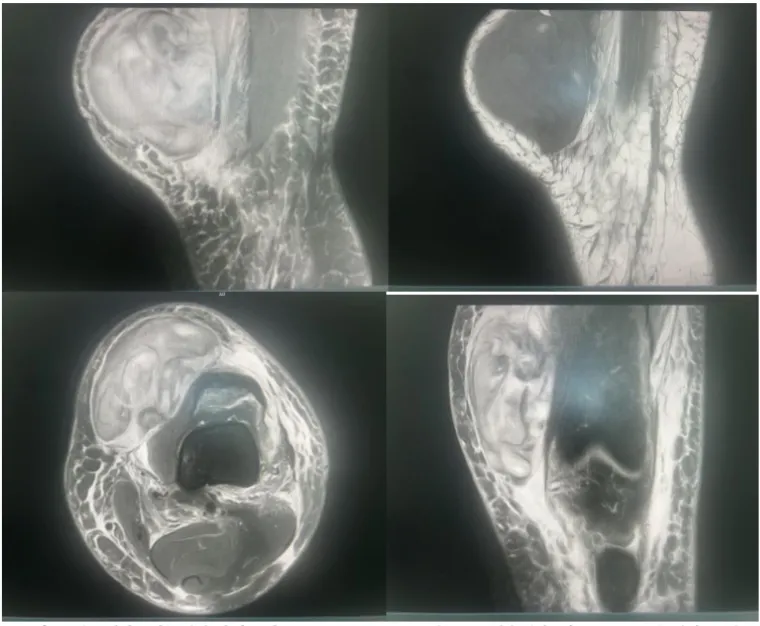

入院后,骨科医护团队积极对患者完善相关检查,患者左膝血肿在进行核磁检查,发现左膝部血肿巨大、皮肤张力高,最长处已达10余公分。如果继续行保守治疗,血肿皮肤持续高张力有皮肤坏死风险。如果按传统方法行血肿切开清除术,切口也将达到10余公分,创伤较大,恢复较慢亦有继发感染风险。

术前MRI显示左侧膝部血肿最长105mm